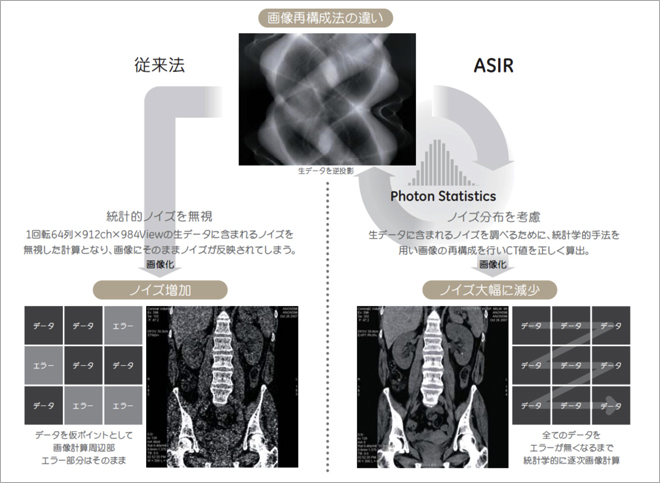

81qKL64RHHL._AC_UF1000,, 冠動脈CT検査におけるGEの最新技術-技術解説 - GEヘルスケア,

冠動脈CT検査におけるGEの最新技術-技術解説 - GEヘルスケア, 冠動脈疾患疑い患者への検査、CT vs.侵襲的冠動脈造影/NEJM,